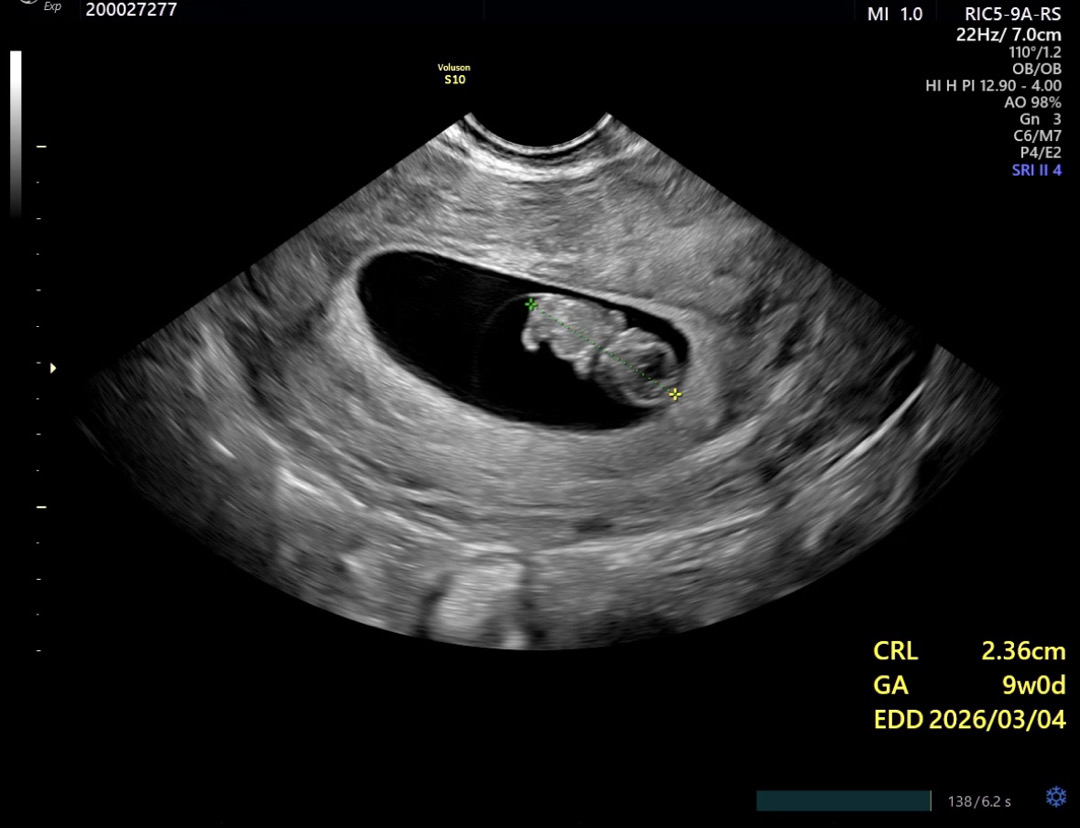

9주 젤리곰 보고왔어요 🥺

오늘 9주차 젤리곰 보고왔어요 ㅎㅎㅎ 오늘 회사에서 안좋은일이 있어서 펑펑 울었어서 걱정했는데 심장두 잘 뛰고있고 잘 크고있대요... 지금까지 입덧먹덧 한거 생각하니 더 뿌듯?하구...ㅋㅋㅋㅋ 그리고 의사쌤이 벌써 뭐가 달린거같기도 하다면서~ 아들을 원해서 별 타격은 없었지만용ㅎㅎㅎ 다들 얼른 젤리곰 보는 시기가 오시길 바랄게요!!!